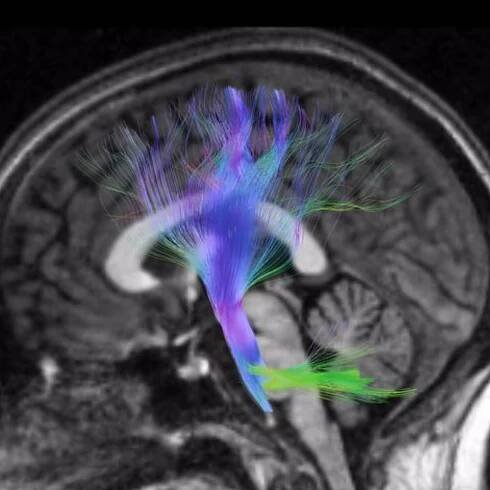

Obsah: Co je nádor a jak vzniká? Nádory mozku a míchy – v čem jsou odlišné od ostatních? Primární nádory mozku – jaký je výskyt? Jaké jsou vyvolávající faktory? Příznaky onemocnění Vyšetřovací metody Léčba primárních mozkových nádorů Léčba…